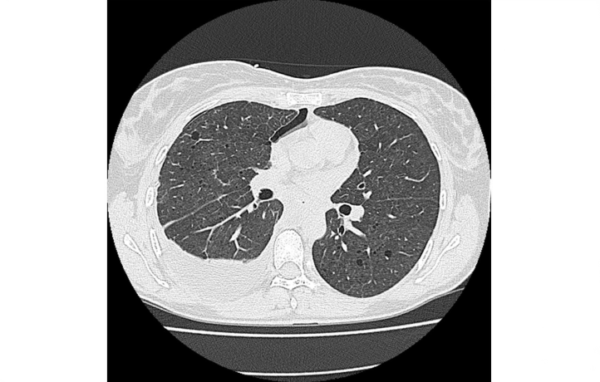

La LAM è caratterizzata da una proliferazione incontrollata di cellule muscolari lisce, non cancerose, che invadono il tessuto dei polmoni, delle vie aeree, dei vasi sanguigni e linfatici. Si tratta di cellule che portano alla degenerazione dei tessuti e causano la formazione di cisti con alterazione della delicata architettura del polmone. La lenta, continua e progressiva sottrazione di tessuto sano preposto agli scambi gassosi e quindi alla respirazione, conduce all’insufficienza respiratoria, all’ossigenoterapia e nei casi più gravi al trapianto di polmone.

I test utili per diagnosticare la LAM sono la TAC del torace, dell’addome e della pelvi, l’emogasanalisi, gli esami della funzionalità respiratoria. Tuttavia una diagnosi certa si acquisisce soltanto con la biopsia chirurgica.

Negli stadi iniziali la radiografia dell’apparato respiratorio può essere significativa; negli stadi avanzati i cambiamenti strutturali dei polmoni sono tali da essere evidenti anche come “polmone ad alveare”.